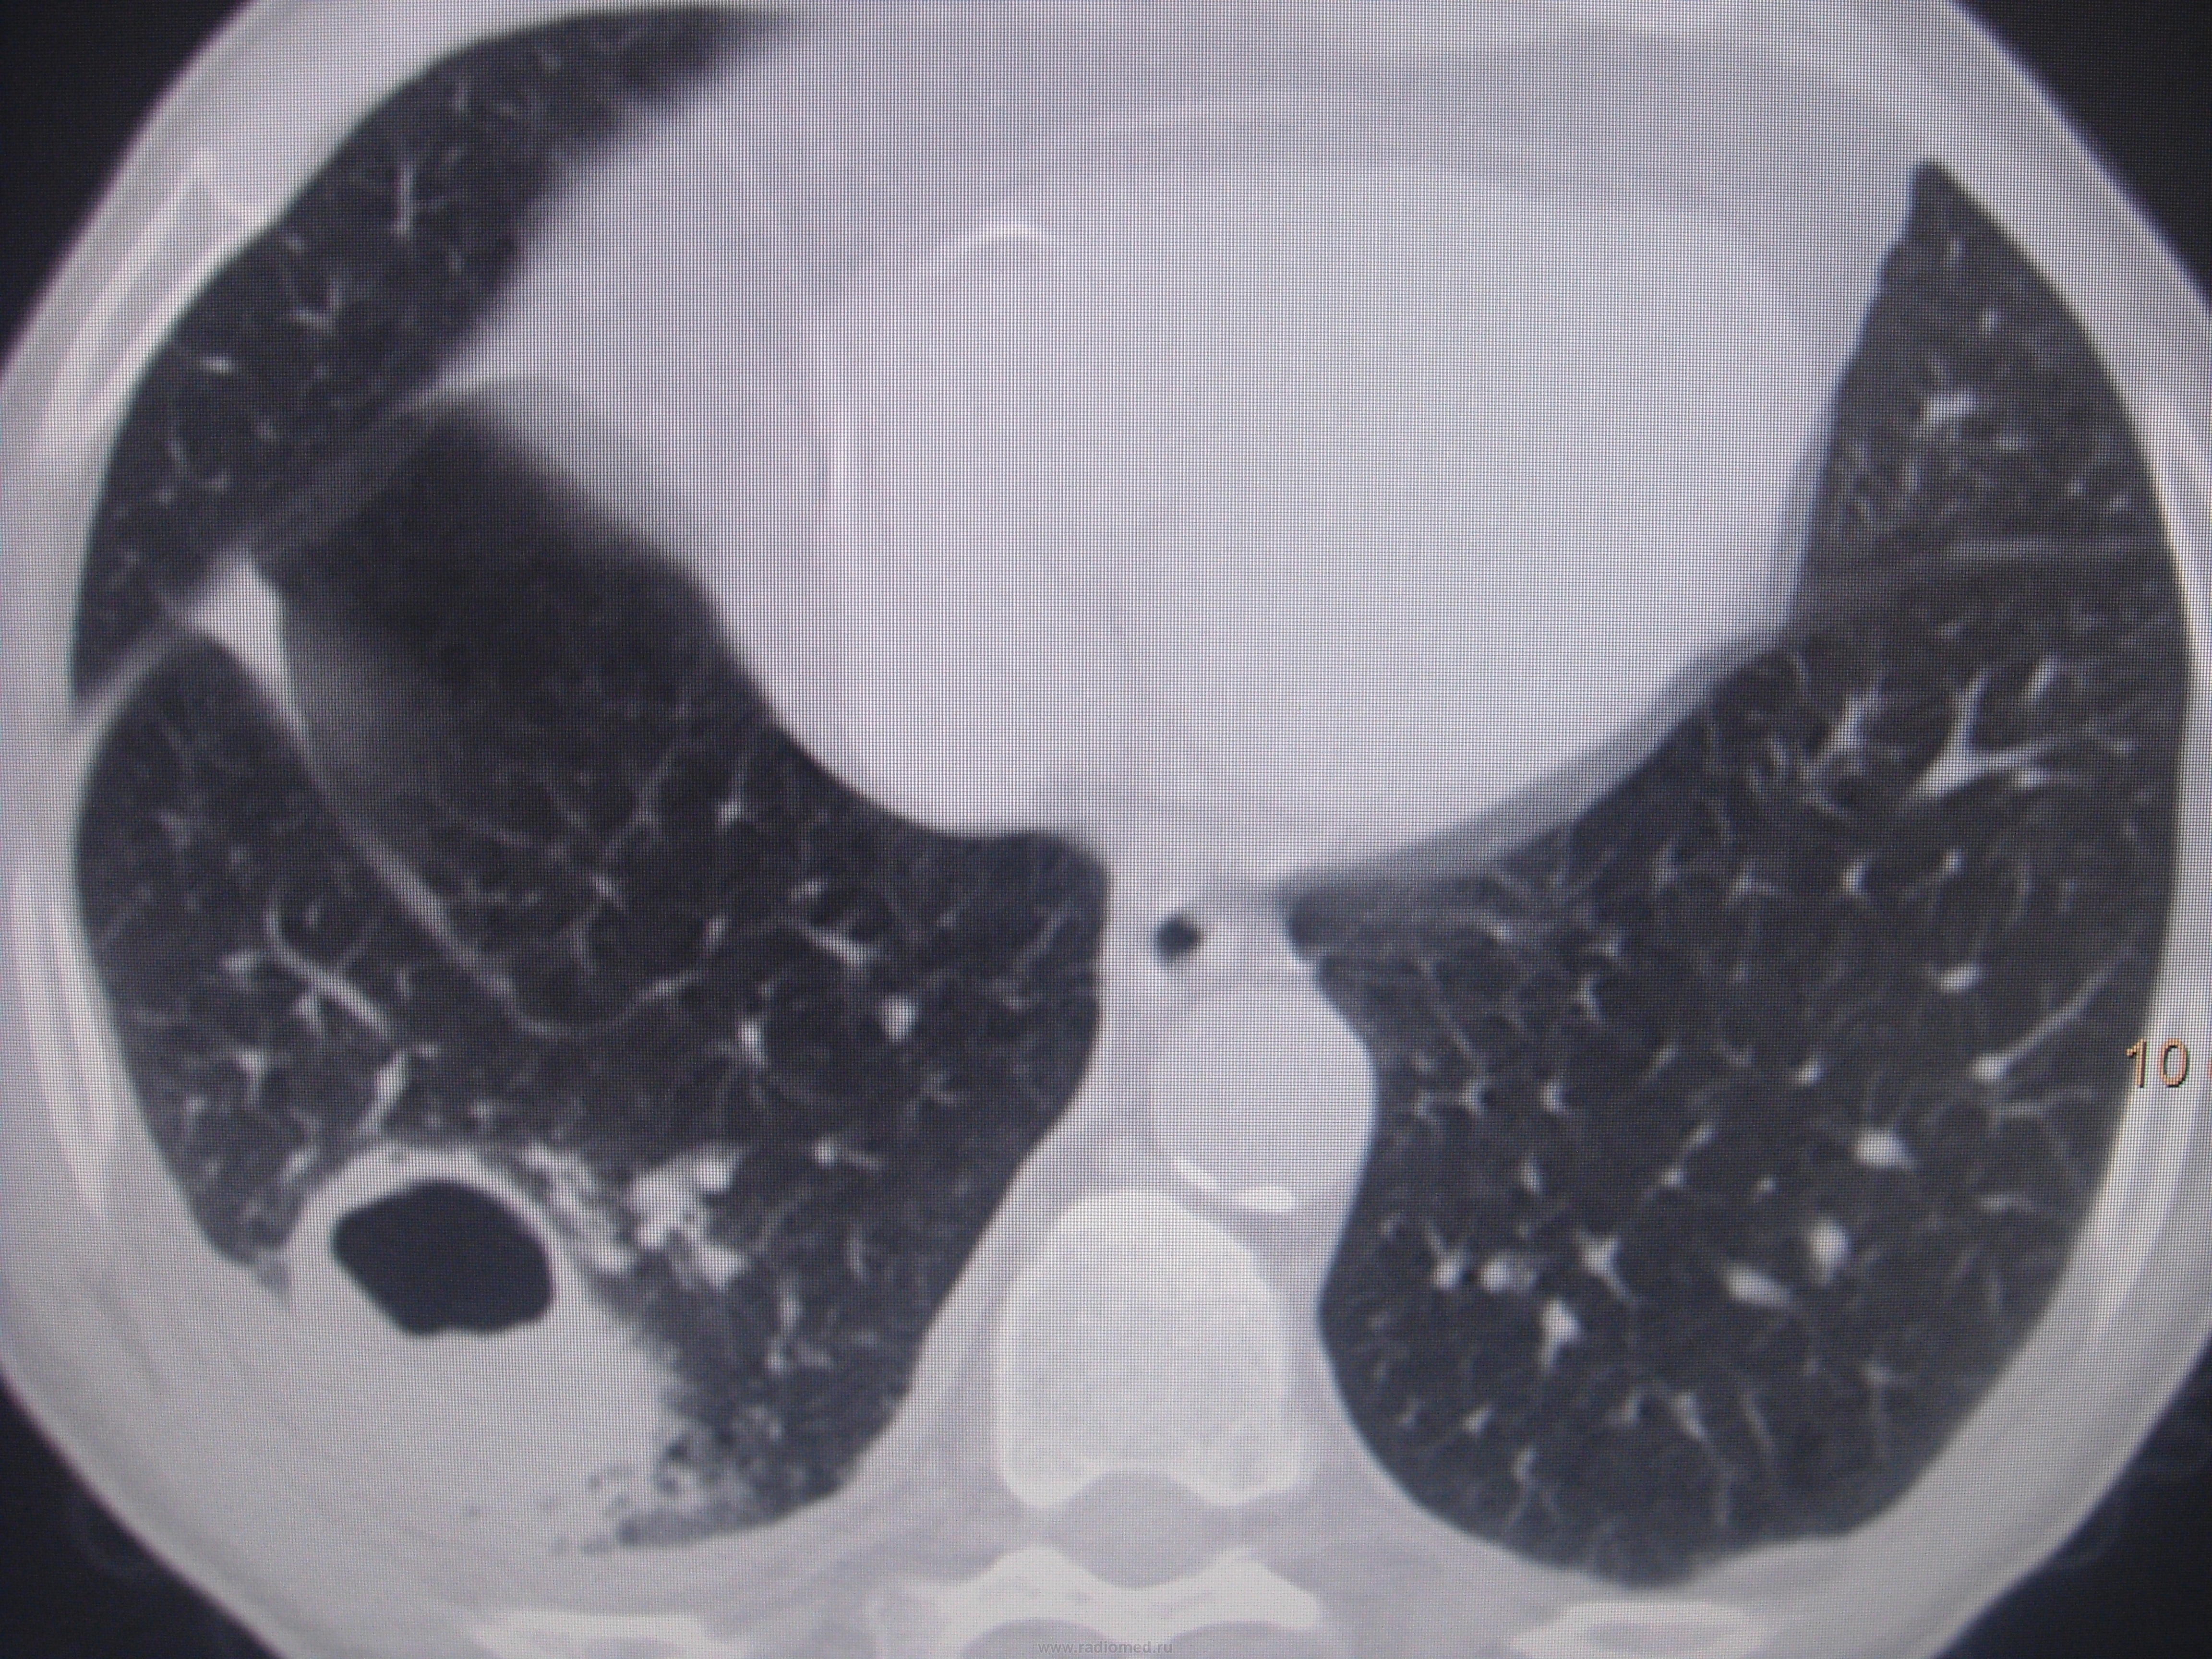

Абсцесс легкого?

Больной лечился у невролога, провели проф ФГ- выявили деструктивную пневмонию, пролечилили, на Р контроле- ухудшение, клиники абсцесса не было, была боль в гр клетке спереди справа. Из анамнеза- лечился оперативно 6-7 лет назад по поводу рака верхней губы, в ООД не наблюдался последние годы. Данные за туб этиологию сомнительны, как мне кажется, очагов отсева по слоям не вижу,  хотя мож не так смотрю. Ваше мнение коллеги, абсцесс это или нет?

Вполне может быть и полостной формой рака с периканкрозной пневмонией. Пока исследуют мокроту на БК, АК и микрофлору с чувствительностью к антибиотикам, пока лечат, придёт время и для КТ-контроля после лечения. В зависимости от рукастости хирургов, можно было б и пропунктировать - но тут в каждом монастыре свой устав)).

По опыту хочу сказать, что в настоящее время классической клиники абсцесса можете и не увидеть. Очень она изменилась. В данном случае контроль  должен помочь. В связи с тем, что стенки имеют разную толщину и вокруг почти нет изменений, больше склоняюсь к полостной форме рака.